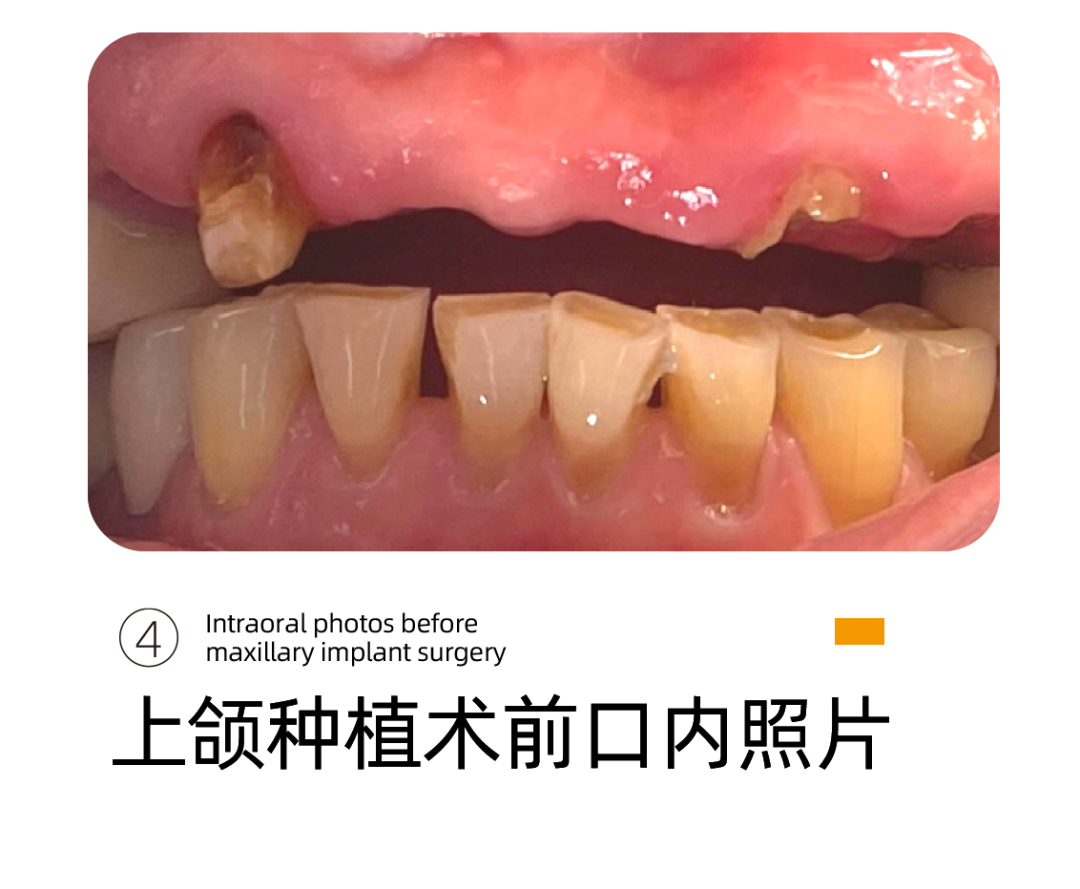

在李雪松医生的建议下,阿姨开始准备做上牙齿的种植。阿姨的上颌牙基本上已经彻底失去了牙齿功能。

这是上颌种植前,阿姨的牙齿状况。